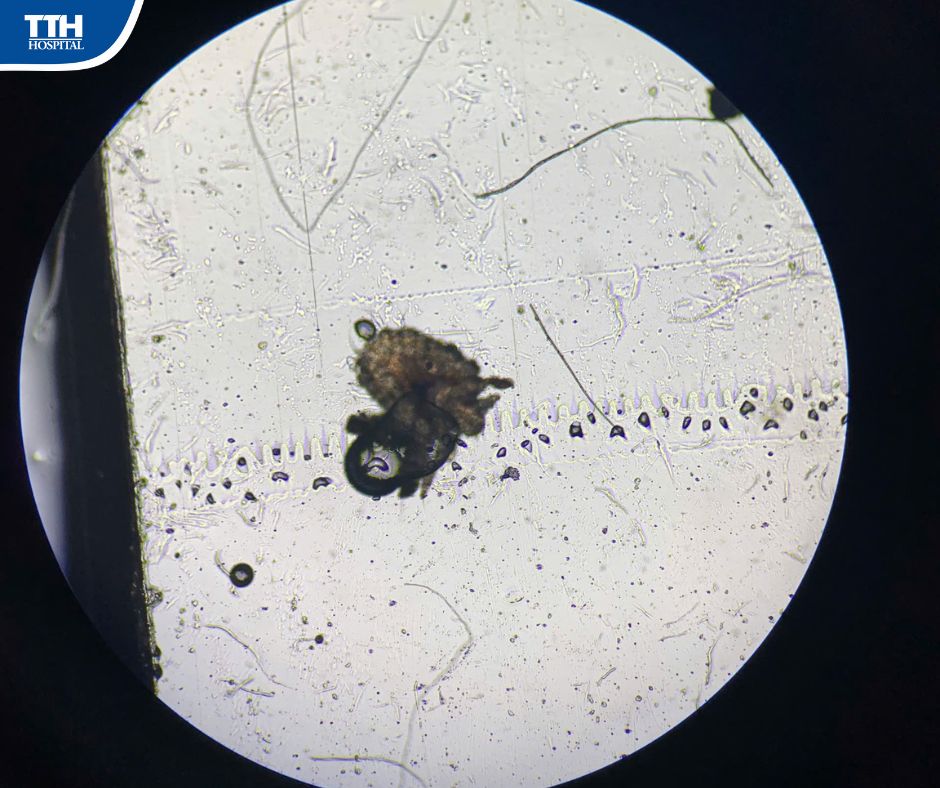

💚 Bé N.P.A (2 tuổi, trú tại xã Hà Linh, tỉnh Hà Tĩnh) được đưa đến Bệnh viện Đa khoa TTH Hà Tĩnh trong tình trạng mí mắt sưng đỏ, ngứa dữ dội, liên tục dụi mắt. Quan sát kỹ dưới kính hiển vi, các bác sĩ phát hiện nhiều chấm nhỏ li ti bám quanh chân lông mi - đó chính là rận mi mắt.